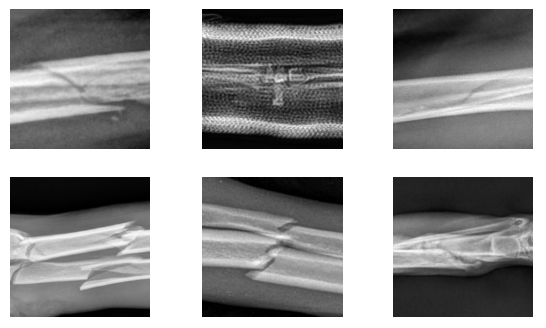

We employ a dual methodology to determine the ideal number of clusters. First, we conduct a systematic sweep over a range of clusters, and use Silhouette Score [50] and Adjusted Rand Index Score [51] to quantitatively evaluate the clustering outcomes. This data-driven approach serves as the first filter in determining the optimal number of clusters. Second, we prioritize interpretability by manually inspecting the images to identify visual features that could serve as natural cluster centers. We aim to ensure that the clusters represent distinct, interpretable categories that reflect the underlying structure of the data. Through this inspection, we identify a set of major visual features that we believe the model should capture. These features include vertical lines, horizontal lines, oblique lines, absence of lines, zoomed-out images, and the presence of medical devices among others.

We ultimately select six clusters. This choice aligns with the major visual features we wish the model to recognize, achieving a balance between optimization and interpretability. Figure 2 showcases a representative sampling of images belonging to each cluster. This categorization helps in understanding the nature of the classifier’s outputs and enriches insights into whether the clusters are being formed based on features that are both interpretable and logically coherent.